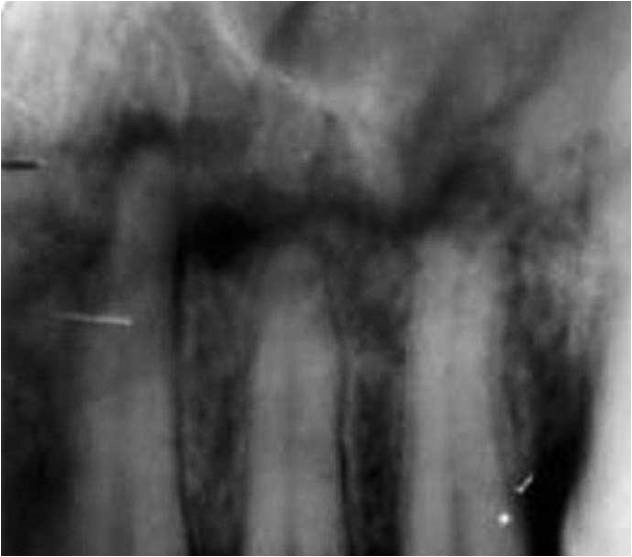

2673. Перелом альвеолярного отростка выше верхушек зубов является